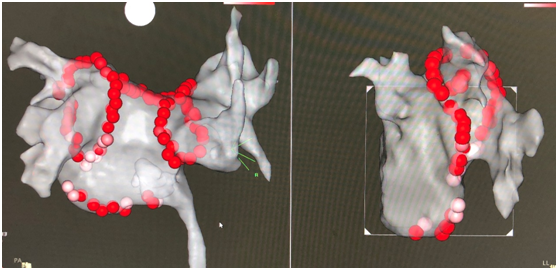

射頻消融示意圖